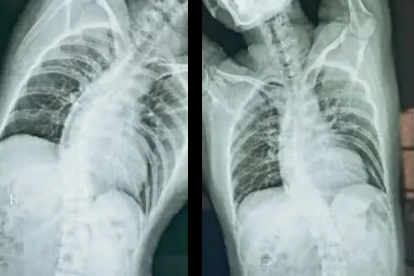

脊椎骨弯曲是一种常见的脊柱畸形,主要包括脊柱侧弯和后凸畸形。发病原因多样,可能与遗传因素、生长发育异常、神经肌肉疾病等有关。早期诊断和规范治疗对改善预后至关重要。